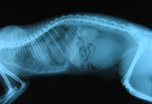

Pomocí dvou RTG snímků, pořízených s odstupem několika hodin, byla odhalena zvětšující se masa v hrudní dutině a bylo vysloveno podezření na brániční kýlu.

Nahoře jsou vyobrazeny vždy dva totožné snímky, vpravo je přerušovanou čárou ohraničen kýlní obsah.

Na snímku 4 je žlutým kolem zvýrazněn přeplněný močový měchýř.

Snímek 5 těsně před operací - kýlní obsah silně utlačuje plíce a srdce.